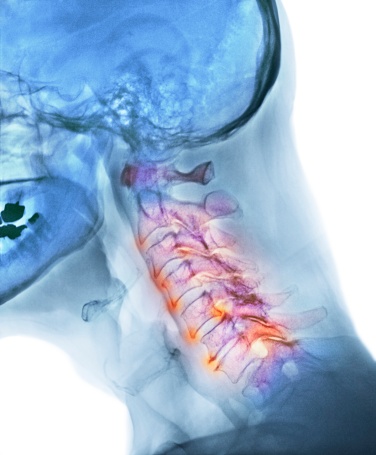

La rectificación cervical es la disminución o desaparición de la lordosis (curva normal fisiológica) de las vértebras cervicales, asociada en muchas ocasiones a cervicalgia o dolor de cuello.

La inversión cervical es una rectificación cervical tan severa, que la curvatura fisiológica que presenta la columna cervical pasa de ser una concavidad posterior a una concavidad anterior. En los accidentes de tráfico importantes, con un latigazo cervical, es típica la inversión de la lordosis cervical.

Grado II: Dolor y contractura muscular moderada, limitación de la movilidad. En las radiografías generalmente se puede apreciar una rectificación de la curvatura normal de la columna cervical (lordosis).

Grado III: Dolor intenso, contractura muscular severa, discapacidad motriz, etc. En las radiografías generalmente se puede apreciar una inversión de la lordosis.